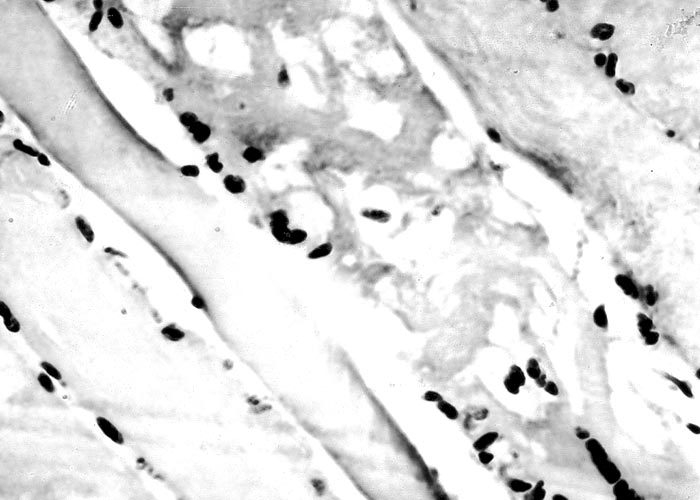

The most complete account of the lesions in vermeersiekte is given by Pienaar et al.113 (1973), who described changes in both the skeletal muscles and oesophagus. Light microscopical examination revealed lesions in randomly distributed individual myocytes or groups of muscle fibres. Affected fibres contained vacuoles of different size into which one or more sarcolemmal nuclei had often intruded (Figures 12 and 13). The sarcoplasm surrounding these vacuoles was in some instances hyalinized (Figure 14). In more chronic experimental cases, the size of the muscle fibres varied, some of the hyalinized fibres being smaller and showing proliferation and centralization of sarcolemmal nuclei. Ultramicroscopical studies showed that the vacuoles in the sarcoplasm were caused by the degeneration of myofibrils in otherwise intact-muscle fibres. The thick myofibrils were first to disappear, resulting in a loss of the A-band (Figure 15), followed by shredding of the remaining filaments, until ultimately all the myofibrils were destroyed (Figure 16). Fine granular material, containing remnants of myofilaments, Z-band material (Figure 16) and swollen vacuolated mitochondria, were evident in such fibres. As a result of the loss in myofibrils the diameter of some of the muscle fibres was reduced.113